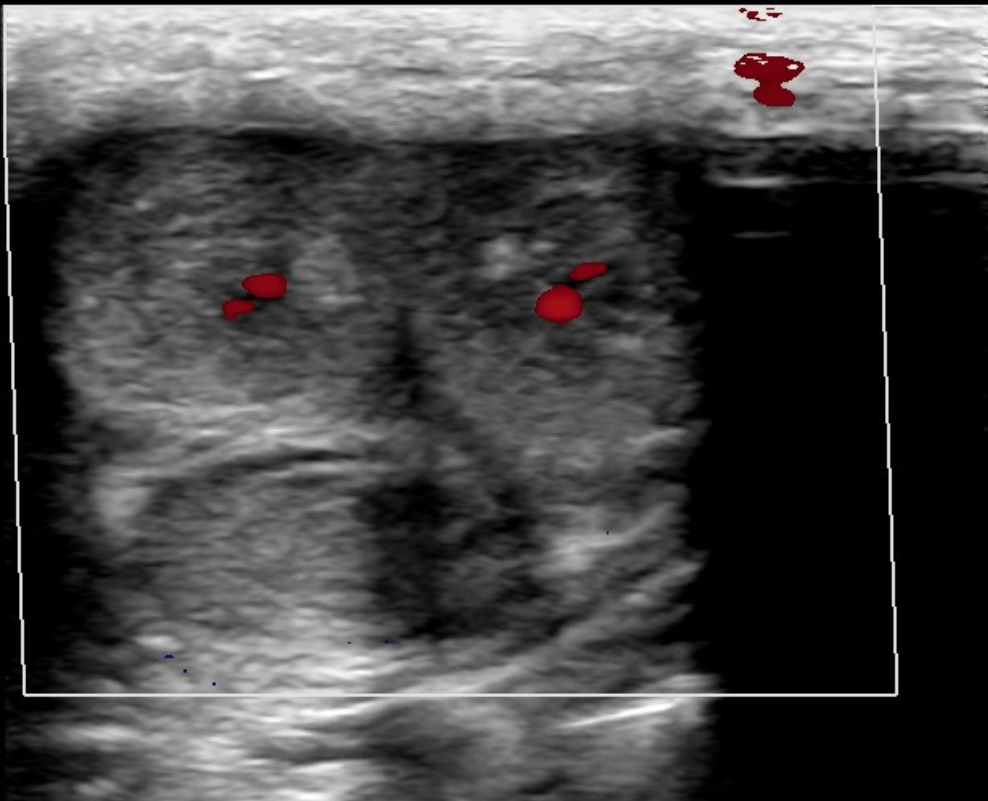

Which of the following is a characteristic of a normal lymph node?

C. thin hypochoic rim with hyperechoic central hilum

Normal lymph nodes are ovoid in shape. They do not demonstrate posterior enhancement. As lymph nodes enlarge with abnormal fluid accumulation, they appear more rounded and hypochoic/anechoic. The "plump" cortex causes decreased visualization of the central hilum. Color Doppler can be used to locate the hilum and main vascular supply. Posterior enhancement is present in structures posterior to abnormal nodes with significant fluid accumulation.

While scanning the thyroid, you identify a 0.6cm ovoid structure outside the thyroid, lateral to the left carotid artery. The structure has a thin hypoechoic rim surrounding a hyperechoic center. These findings are most suggestive of:

D. normal lymph node

Normal lymph nodes are ovoid in shape. They do not demonstrate posterior enhancement. As lymph nodes enlarge with abnormal fluid accumulation, they appear more rounded and hypoechoic/anechoic. The "plump" cortex causes decreased visualization of the central hilum. Color Doppler can be used to locate the hilum and main vascular supply. Posterior enhancement is present in structures posterior to abnormal nodes with significant fluid accumulation.

Find the normal lymph node

A normal lymph node is oval in shape and demonstrates a thin hypoechoic rim of tissue around an echogenic hilum. Abnormal lymph nodes demonstrate a more rounded shape, thickened cortex that can appear anechoic. and there is loss of differentiation of the hilum.